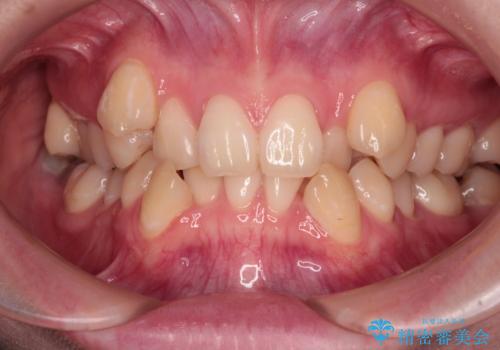

50代女性 八重歯を矯正治療 歯並びの中等度のがたつき

マウスピース矯正が煩わしい ワイヤー装置での非抜歯矯正

担当医 藤巻太一朗